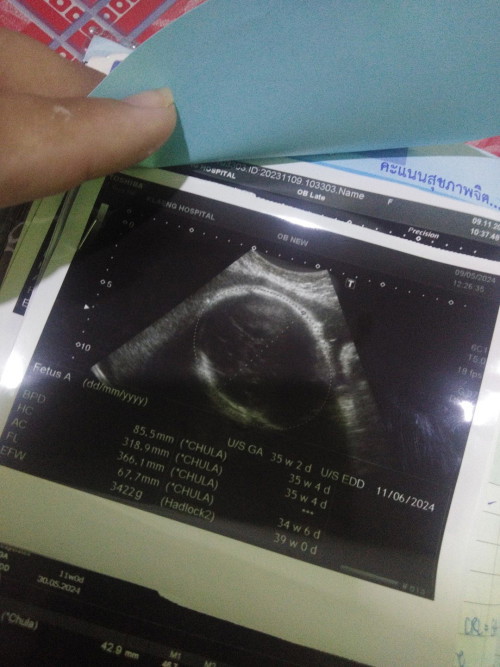

น้อง35 w แล้วค่ะ ลูกสาวคนแรกของแม่จ๋าพ่อปืน